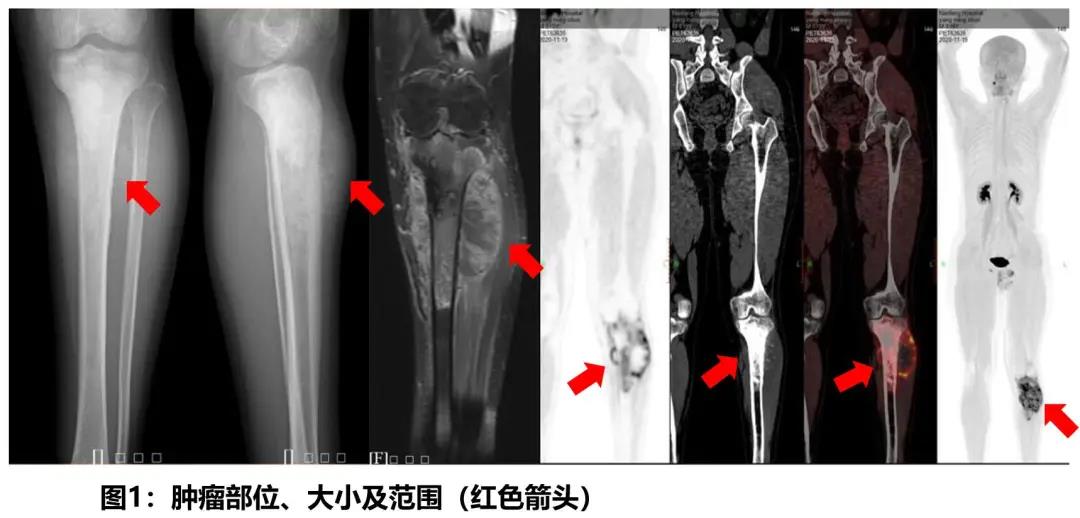

The patient is a 19-year-old boy. When he visited the Department of Orthopedic Trauma of Nanfang Hospital, he complained the pain in his left leg. The X-ray examination showed that the tumor had invaded more than half length of his left tibia, and particularly, even invaded the articular surface of tibia, which was a rare situation in osteosarcoma. In this case, amputation is a common solution. However, both the patient himself and his mother wanted to keep his leg. After a thorough communication with the patient and his family, we decided to go on a standard treatment protocol - neoadjuvant chemotherapy + surgery + postoperative chemotherapy.

After two rounds of preoperative neoadjuvant chemotherapy and one week of preoperative preparation, the surgery which was led by Dr. Yu Bin, Head of the Department of Orthopedic Trauma of Nanfang Hospital was performed by the Bone Tumor Subspecialty Group in five steps - "left tibia tumor bone resection + liquid nitrogen for cryotherapy treatment + removed tumor bone replantation + tumorous type knee joint prosthetic replacement + dual plate internal fixation of tibia". After eight hours, the surgery was completed smoothly. Twenty days after the surgery, the patient was discharged from the hospital. He will receive further comprehensive treatment in the next step.